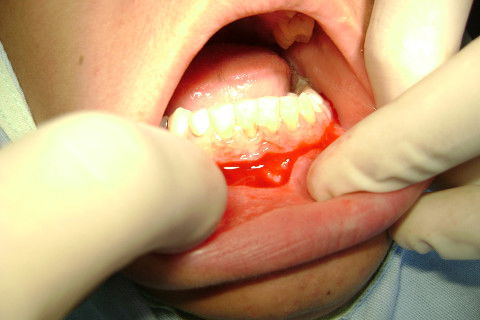

Odontossecção parcial da coroa com broca 703 PM.

Fragmento da coroa após ser fraturado com a Seldin Reta,

Elevação da porção radicular com o Molt 9.

O restante de capuz pericoronário foi removido e a região irrigada com soro.